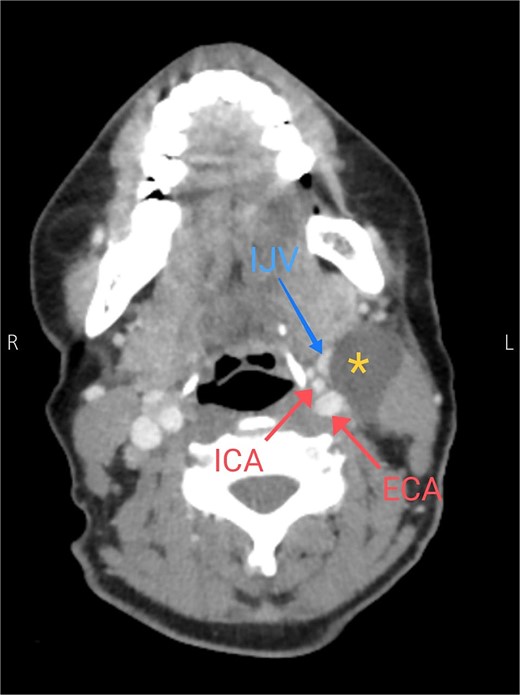

Soft tissue ultrasound revealed a well-demarcated, oval-shaped, homogeneously hypoechoic with internal debris mass and posterior acoustic enhancement, measuring about 3.8 × 4.7 cm. Axial (Fig. 2), sagittal (Fig. 3), and coronal (Fig. 4) neck computed tomography (CT) scans with intravenous (IV) contrast confirmed the presence of a cystic mass measuring 4.2 × 3.1 cm with centered fluid density and thin walls, lying over the common carotid artery (CCA), internal carotid artery (ICA), and external carotid artery (ECA), partially compressing the internal jugular vein (IJV) and ECA coinciding with second branchial cleft cyst.

Axial CT neck scan showing the branchial cleft cyst compressing the IJV and adjacent to the external and internal jugular arteries. Asterisk: branchial cleft cyst, arrows: external and internal carotid arteries, blue arrow: IJV.